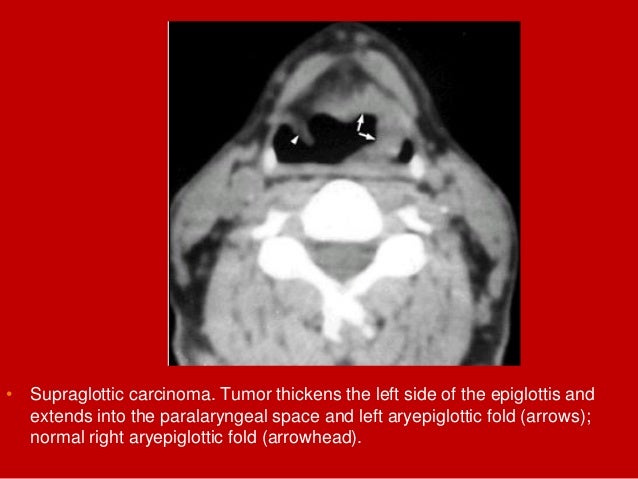

22. 22. • Supraglottic carcinoma. Tumor thickens the left side of the epiglottis and extends into the paralaryngeal space and left aryepiglottic fold (arrows); normal right aryepiglottic fold (arrowhead).